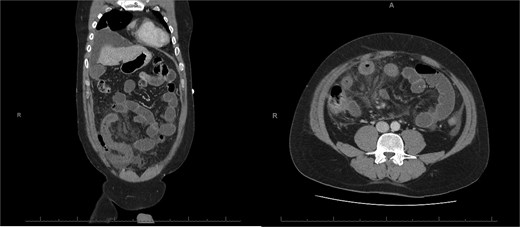

A 76-year-old female with a 3-day history of left upper abdominal pain, vomiting, and haematochezia. Her history included pulmonary embolism, multiple deep vein thromboses, with no ongoing anticoagulation, and an open partial colectomy for complicated diverticulitis a decade earlier. On admission, she was afebrile but tachycardic and showed localized tenderness in the left hypochondrium. Laboratory revealed leucocytosis with a white blood cell count (WBC) of 12 G/L, elevated C-reactive protein (CRP) of 46 mg/L, and hyperlactatemia of 2.6 mmol/l. Enhanced computed tomography (E-CT) revealed jejunal venous ischemia in the left upper quadrant, secondary to extensive porto-mesenteric thrombosis with reduced bowel wall enhancement, distention, and free intraperitoneal fluid (Fig. 1). She was managed conservatively with unfractionated heparin (UFH) with a bolus of 5000 U/l followed by 30 000 U/l/24 h (target INR 0.35–0.7), Piperacillin-Tazobactam, and bowel rest. After 48 h of monitoring in the intensive care unit (ICU), she exhibited marked biological and clinical improvement. E-CT on the third day showed restored bowel wall enhancement and stable porto-mesenteric thrombosis (Fig. 2). She was discharged on therapeutic low molecular weight heparin (LMWH) with enoxaparin sodium 120 mg every 12 h. At the 3-month follow-up, E-CT revealed near-complete thrombus resolution, without intestinal sequelae (Fig. 3).

Three-month E-CT of the first patient showing nearly complete thrombosis resolution, with no signs of intestinal distress.